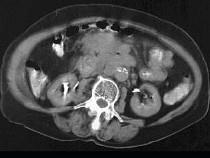

问题 女,28岁,腹痛,恶心呕吐,大便潜血阳性,轻度腹胀,中腹部可扪及一不规则肿块,影像表现如图,最可能的诊断是()

选项 A.小肠腺癌 B.小肠非霍奇金淋巴瘤 C.小肠Crohn病 D.小肠结核 E.腹膜后淋巴结结核

答案 B